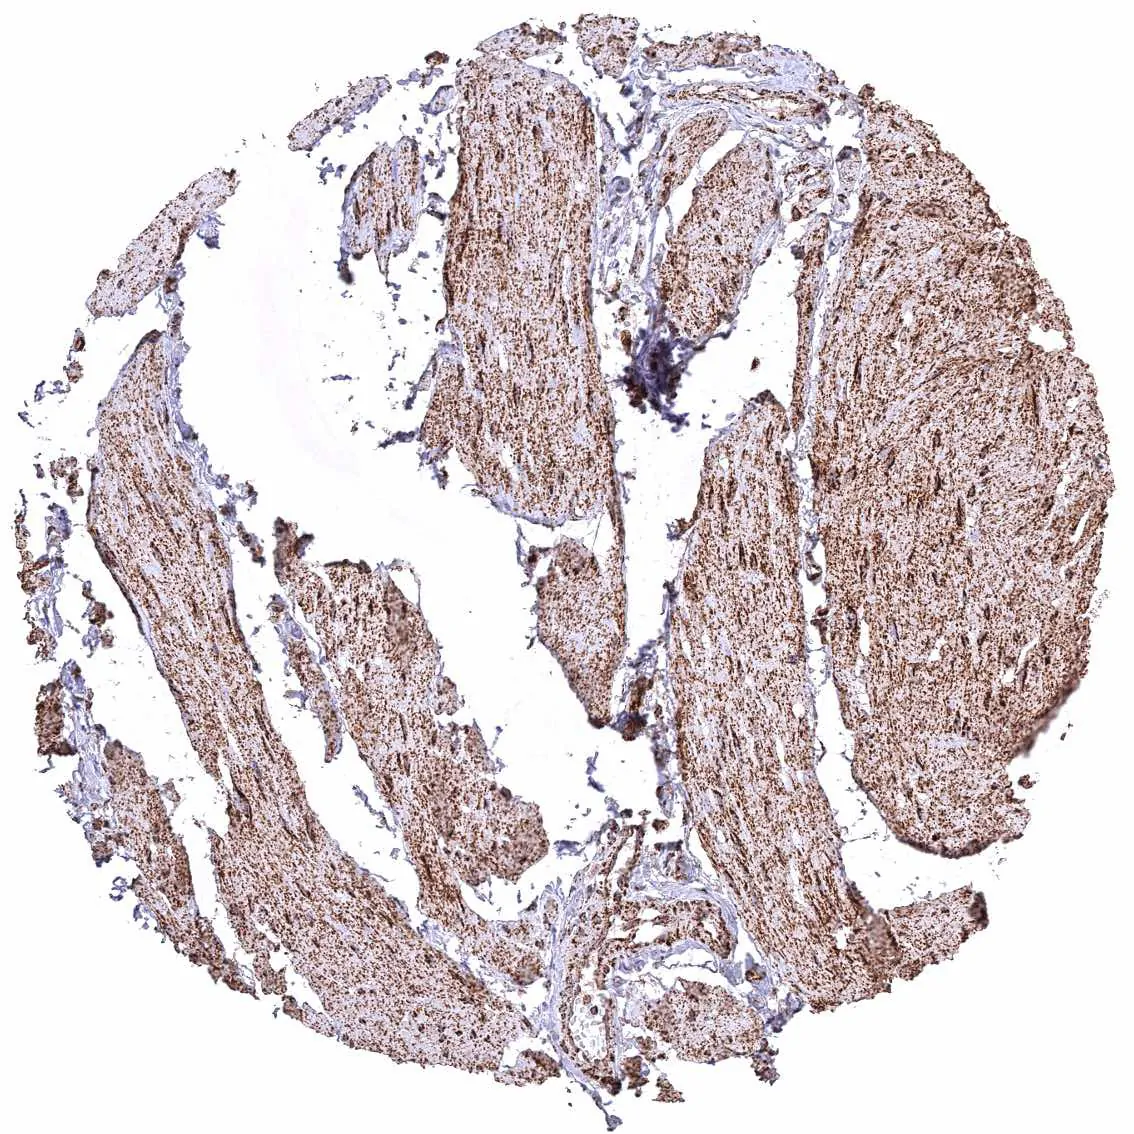

Skeletal muscle